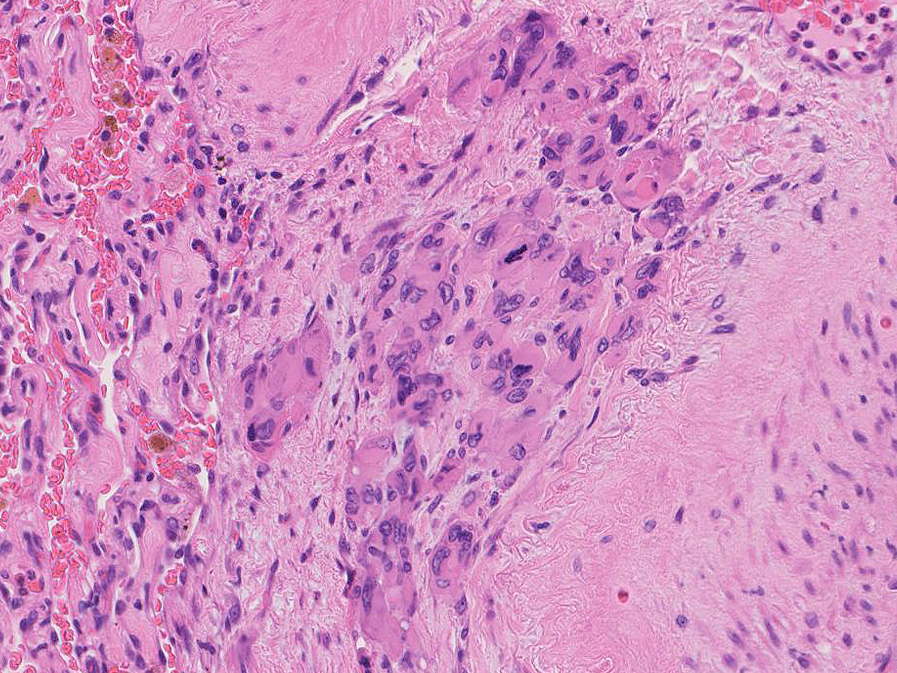

hyperchromaticな類円ないし多角の核で好酸性の広めの細胞質をもつ上皮様細胞が増殖している。右図では血管内を占拠するように腫瘍細胞が認められる。